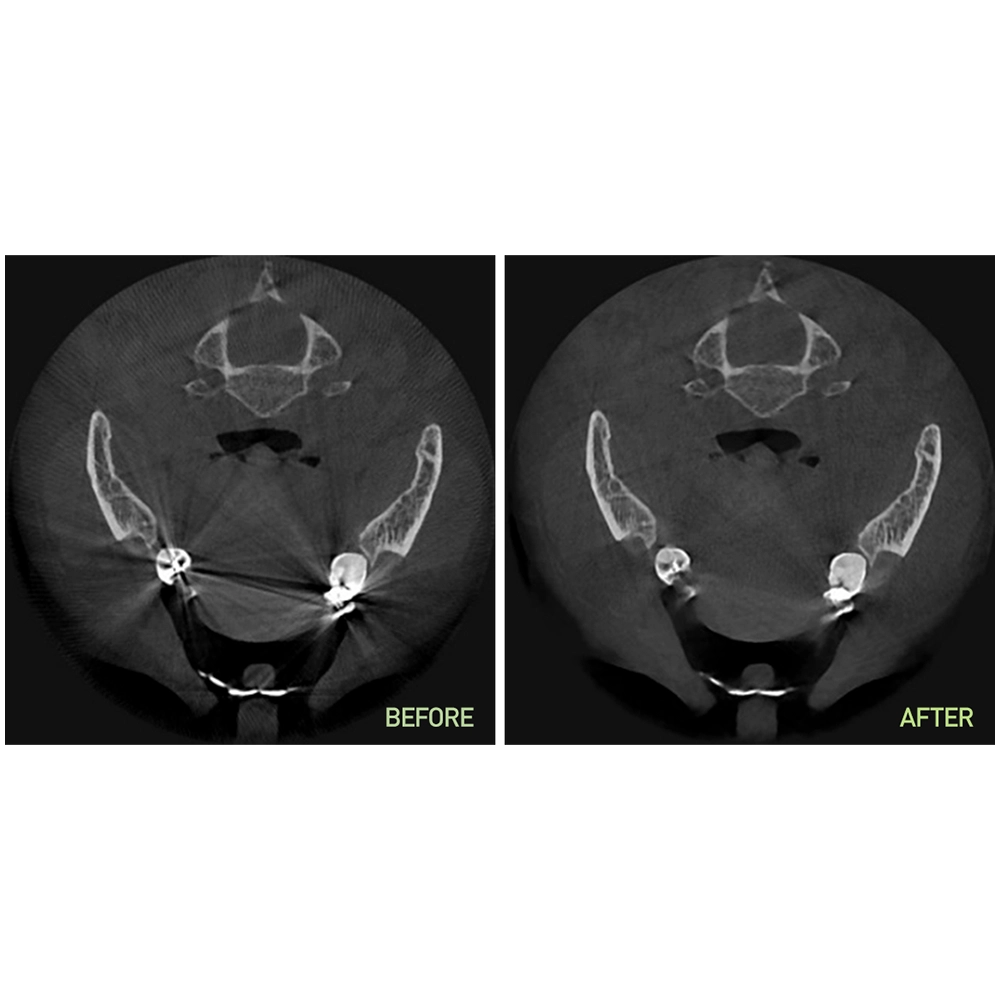

- SMARF™ (Smart Metal Artifact Reduction Function): Claritate îmbunătățită a imaginii prin tehnologia inteligentă de eliminare a artefactelor metalice.